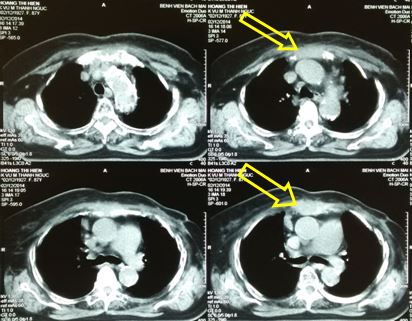

Hình 1. Hình ảnh CT ngực: khối u vú trái tiến triển xâm lấn thành ngực, kích thước 6x7 cm (Vòng tròn đỏ)

-          Sau 3 tháng điều trị xạ trị kết hợp Fulvestrant, trên lâm sàng bệnh nhân ổn định, hết đau ngực, u thành ngực thoái triển gần hết. Trên phim chụp CT ngực: khối u nhỏ lại, kích thước khoảng 2,5x1,5 cm (đầu mũi tên vàng)

Hình 2. Hình ảnh CT ngực sau điều trị 3 tháng: khối u nhỏ lại, kích thước khoảng 2,5x1,5 cm (đầu mũi tên vàng)

-          So sánh trước và sau điều trị: